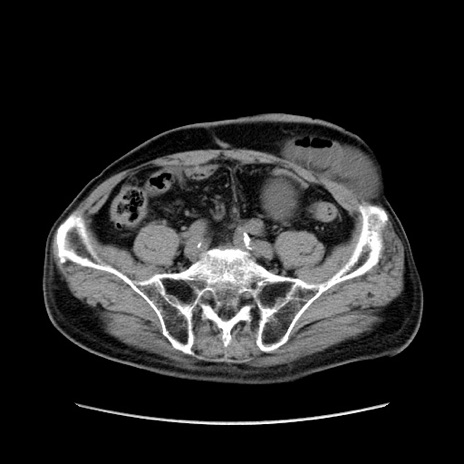

症例24(横断像)

【症例】80歳代男性

【主訴】左側腹部痛、嘔吐

【現病歴】本日早朝より左腹部に痛みあり。昼頃嘔吐認めたため、救急要請。

【既往歴】直腸癌(Mile手術)、胆摘

【身体所見】意識清明、BT 35.9℃、BP 221/93mmHg、SpO2 97%(RA) 、腹部:左ストーマ周囲に限局性の腹部膨隆あり。 膨隆部自発痛・圧痛あり・軟。

【データ】WBC 7700、CRP 0.09